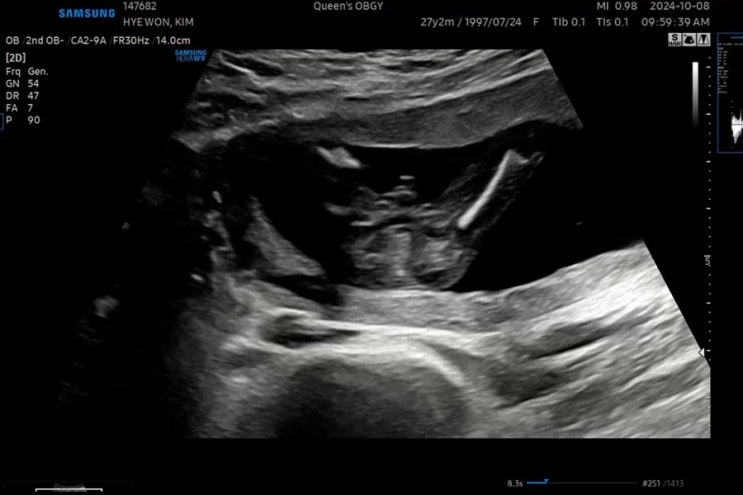

[임신 이야기_7] 임신 10주 ~ 14주 차 이야기_1차 기형아 검사(NT 검사)

사실 이 시기에는 하루 종일 '미뇽이 성별이 뭘까?' 하고 생각했던 시기 검색을 매번 했다.ㅋㅋ...